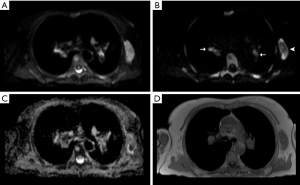

To facilitate anatomical localization of lymph nodes, breath-hold axial T1-weighted MR images, matched to the same imaging field of view and slice thickness of the WB-DWI were also acquired using the following imaging parameters: T1 fast low angle shot, matrix =256×105, slice thickness =5 mm, TR =386 ms, TE =4.8 ms, flip angle =70°, number of averages =1. Figure 1 shows typical images obtained for a patient with lymphoma using the MRI study protocol.